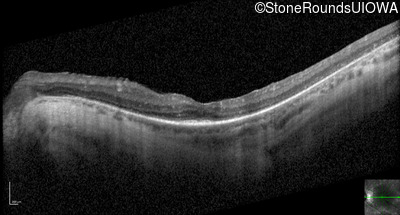

Optical Coherence Tomography - Right - 20/50

Exemplar / OCT Stack

OCT Stack